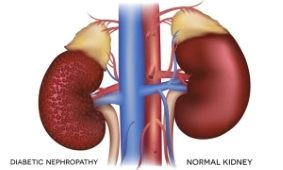

Kidney disease is a common problem affecting about 10% of the world’s population. The kidneys are small but powerful bean-shaped organs that perform many important functions. They are responsible for filtering waste products, releasing hormones that regulate blood pressure, balancing fluids in the body, producing urine, and many other essential tasks. There are various ways in which these vital organs can become damaged. Diabetes and high blood pressure are the most common risk factors for kidney disease. However, obesity, smoking, genetics, gender, and age can also increase the risk. Uncontrolled blood sugar and high blood pressure cause damage to blood vessels in the kidneys, reducing their ability to function optimally.

When the kidneys aren’t working properly, waste builds up in the blood, including waste products from food. Your kidneys filter waste and extra fluid out of your blood so they can be removed from your body in your urine. When your kidneys stop working and can no longer do their job, it’s called kidney failure.

It may even develop into Chronic Kidney Disease, Kidney Damage or Infection, Bladder Damage, and Bladder Stones